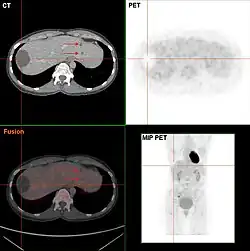

Da eine Leberzyste in den meisten Fällen symptomlos ist, ist sie meist ein Zufallsbefund bei einer Ultraschalluntersuchung. Bei vorhandenen Symptomen oder Komplikationen erfolgt die Diagnose mittels bildgebender Verfahren, meist mittels Ultraschall oder Computertomographie. Dabei können nichtparasitäre von parasitären Leberzysten unterschieden werden.

- Intraduktale papilläre Neoplasie des Gallengangs: Aufstau des Gallengangs, im CT-Enhancement in der arteriellen Phase

- Zystische Lebermetastase: dicke, knotige Wand, Septen

- Hepatische alveoläre Echinococcose: unregelmäßige Ränder, mehrkammerig, zum Teil zentrale Verkalkung[8][9]